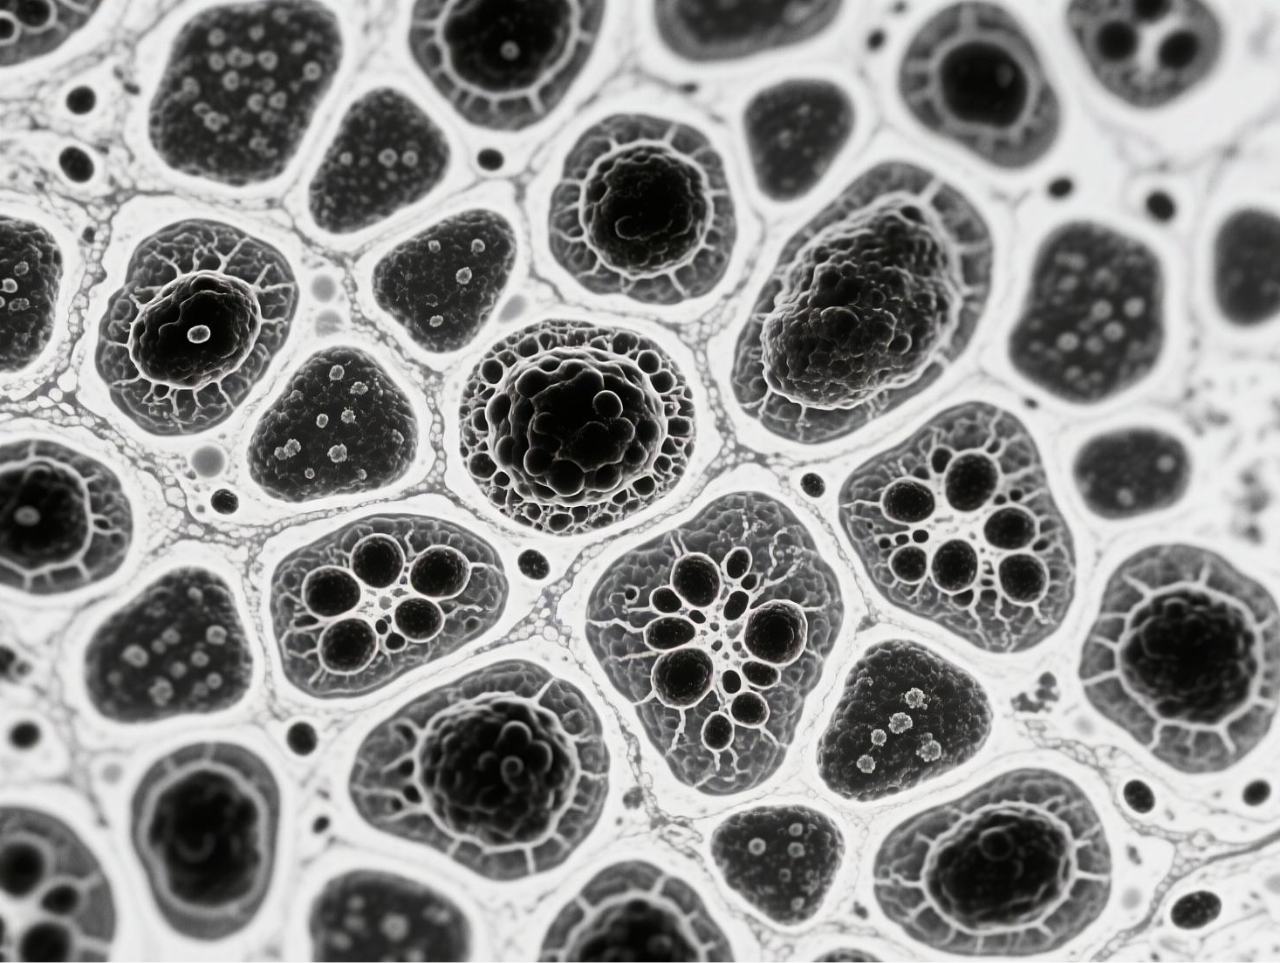

圖 BCG-MBs的制備與表征

臺式掃描電鏡在本研究中發(fā)揮了關鍵的表征作用,為微氣泡系統(tǒng)的結(jié)構(gòu)驗證提供了直觀而精確的證據(jù)。研究團隊使用澤攸科技ZEM18臺式掃描電鏡對凍干后的BCG-MBs進行金濺射鍍膜處理后,在不同放大倍數(shù)下觀察其表面形態(tài),清晰地展示了微氣泡規(guī)則的球形結(jié)構(gòu)以及BCG在微氣泡表面的不規(guī)則分布狀態(tài)。這一表征不僅確認了微氣泡制備工藝的成功,還直觀揭示了BCG在微氣泡中的物理分布特征,為理解藥物釋放機制提供了結(jié)構(gòu)基礎。掃描電鏡圖像作為重要的形態(tài)學證據(jù),有力支持了后續(xù)對微氣泡浮力特性、藥物釋放行為及生物效應的分析,是連接材料設計與功能驗證的關鍵環(huán)節(jié)。